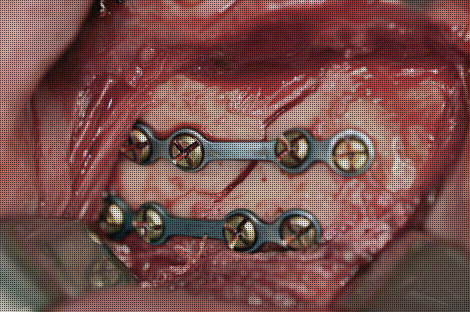

L’intervento chirurgico per una frattura facciale viene di norma eseguito in anestesia generale e consiste nella riduzione della frattura cioè il ripristino della corretta posizione spaziale dei monconi fratturati, e la stabilizzazione per consentire la guarigione nella posizione corretta.

La stabilizzazione delle fratture avviene con placche e viti in titanio che consentono una fissazione rigida e stabile dello scheletro facciale.